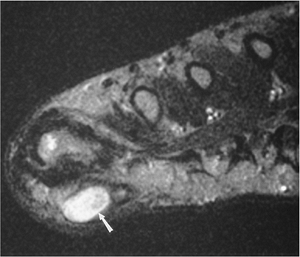

FIGURE 6-66 Axial T1-weighted image demonstrating a Morton’s neuroma (arrow).